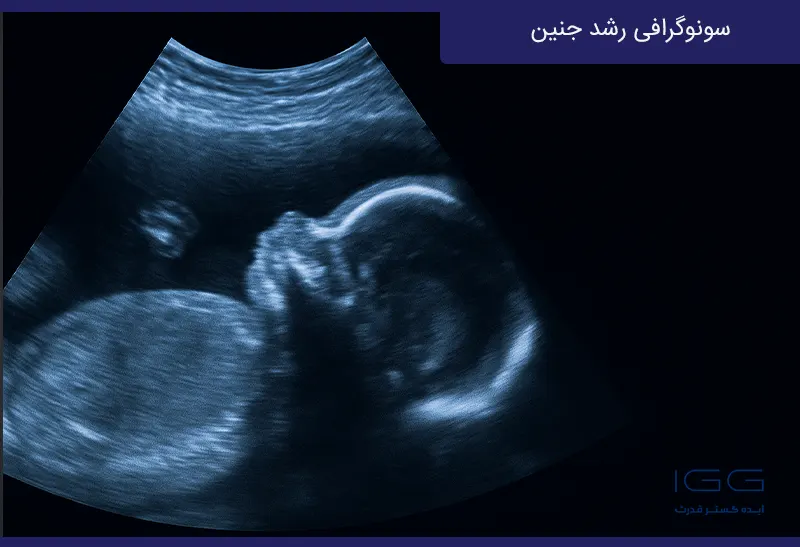

در دوران بارداری، رشد و سلامت جنین از مهمترین دغدغههای مادران و پزشکان است. یکی از روشهای علمی و قابلاعتماد برای ارزیابی وضعیت جنین، سونوگرافی بارداری و بهویژه سونوگرافی رشد جنین است. این روش با استفاده از امواج فراصوت، اطلاعات دقیقی درباره اندازه، وزن، موقعیت و حتی جریان خون جنین در رحم مادر ارائه میدهد.

سونوگرافی رشد جنین نوعی تصویربرداری پزشکی است که برای بررسی روند رشد و تکامل جنین در رحم مادر انجام میشود. در این روش، دستگاه سونوگرافی با ارسال امواج صوتی بیضرر، تصویری زنده از جنین ایجاد میکند. پزشک متخصص با بررسی این تصاویر، میتواند قد، وزن، قطر دور سر و اندازه شکم جنین را محاسبه کرده و وضعیت او را با استانداردهای رشد مقایسه کند.

سونوگرافی رشد جنین و IUGR با استفاده از امواج اولتراسوند انجام میشود و روشی کاملاً ایمن، غیرتهاجمی و بدون درد است. در این روش، پزشک یا کارشناس سونوگرافی با قراردادن پروب (مبدل) روی شکم مادر، امواج صوتی را به درون رحم میفرستد. این امواج پس از برخورد با اندامهای جنین بازتاب پیدا کرده و به تصویر زندهای از داخل رحم تبدیل میشوند.